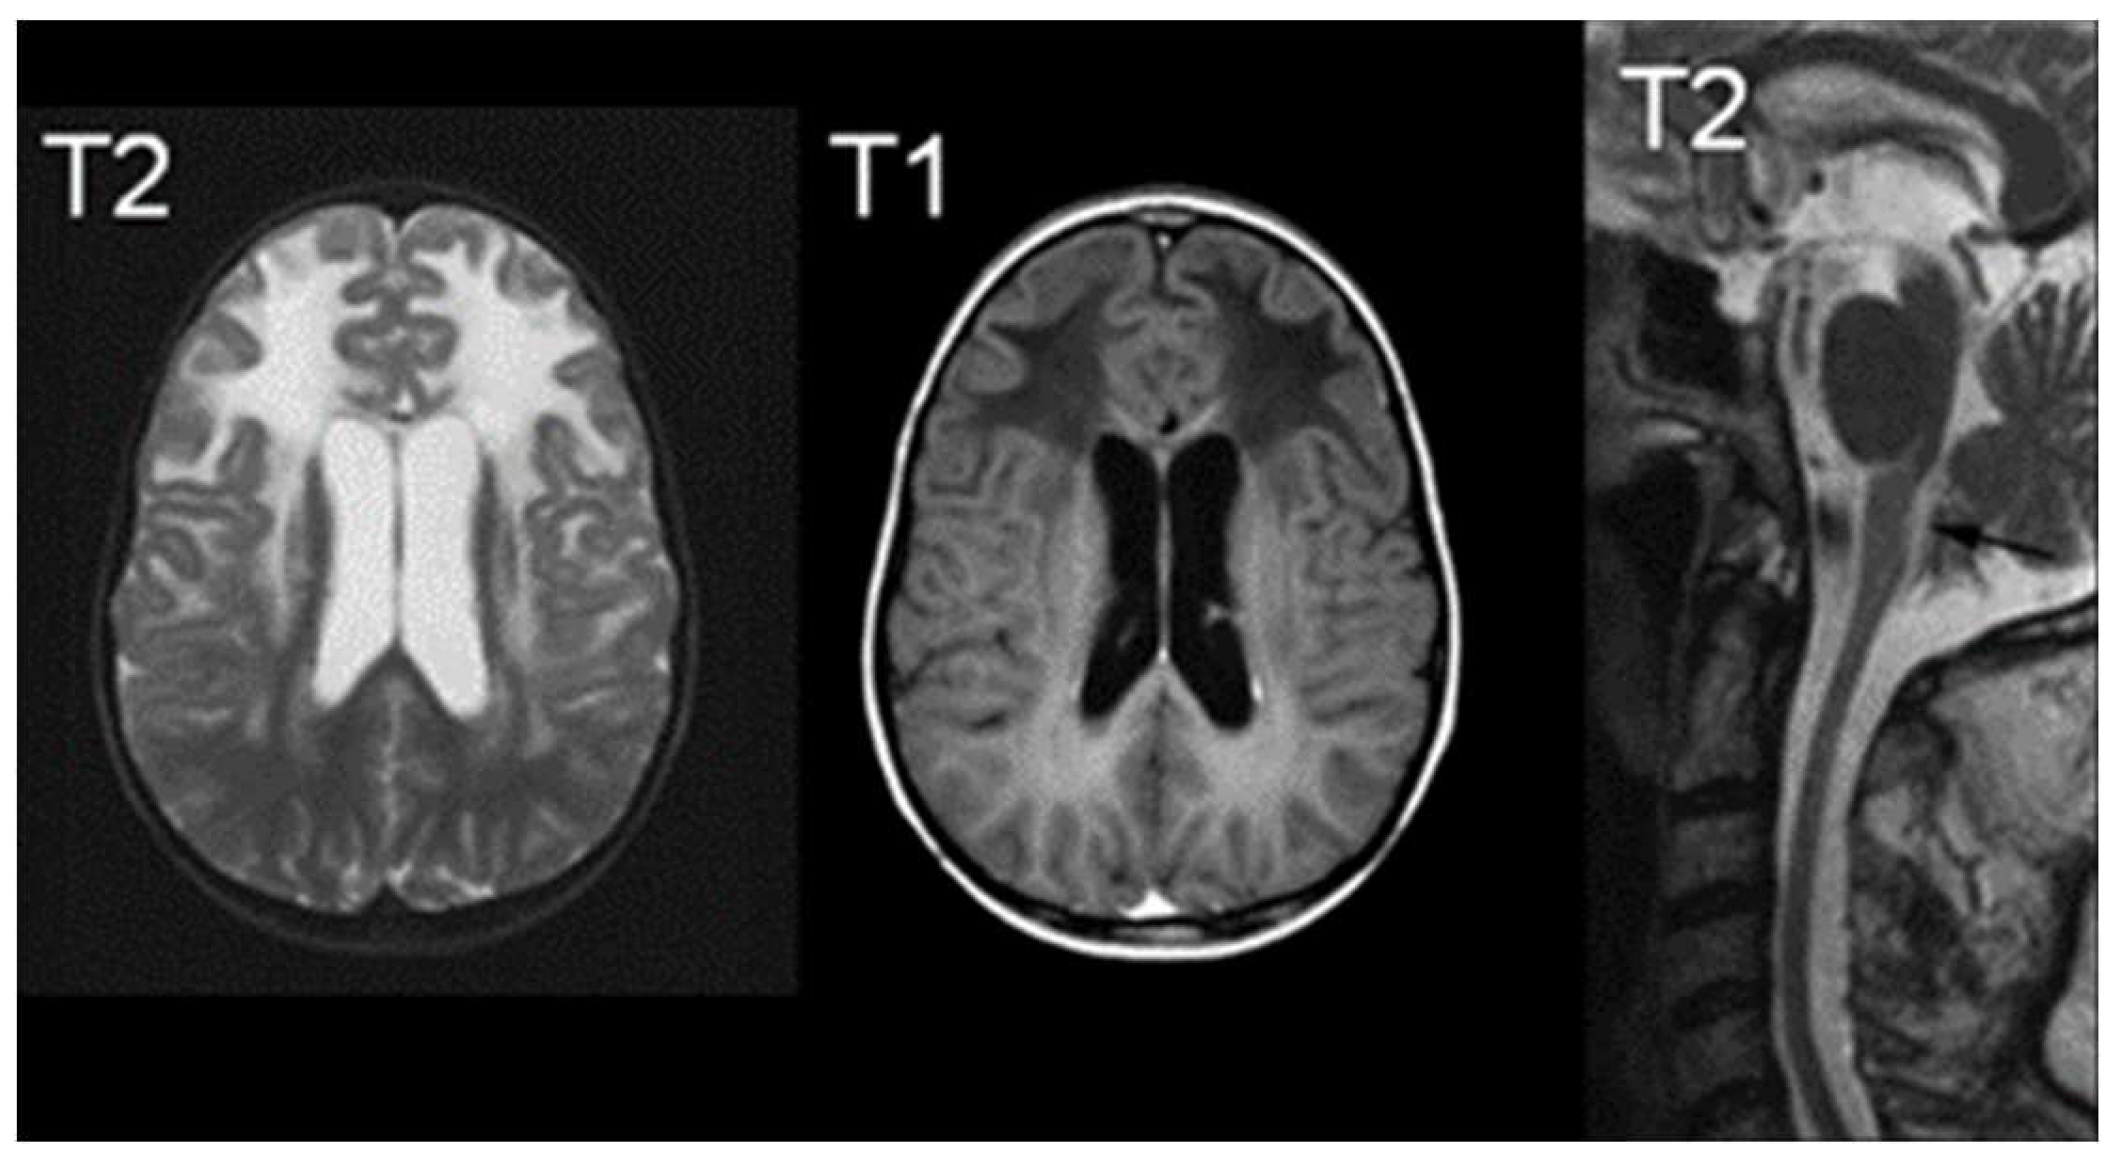

In terms of imaging, MRI findings typically consist of abnormal signals from the frontal white matter, the periventricular rim, or various structures such as the caudate head, thalamus, and brain stem [65]. As demonstrated in Figure 4, MRI findings indicate increased T2-weighted signal intensity, and decreased T1-weighted signal intensity [66]. Van der Knaap et al defined five MR imaging criteria of which four should be met for an imaging-based diagnosis: extensive cerebral frontal white matter abnormalities, periventricular rim with decreased T2 signals and increased T1 signals, basal ganglia and thalami abnormalities, brain stem abnormalities, and contrast enhancement of one or more of the following: ventricular lining, periventricular rim of tissue, the white matter of the frontal lobes, optic chiasm, fornix, basal ganglia, thalamus, dentate nucleus, and brain stem structures [65]. Hindbrain structural abnormalities, such as the brainstem are characteristic of later onset presentation, showing signs of atrophy of the medulla and cervical spinal cord [60].

Figure 5. MRIs characteristic of Alexander Disease; The right image demonstrates an increased signal of T2, the middle image demonstrates a decreased signal of T1, and the right image is a T2 midline sagittal section demonstrating atrophy [66].